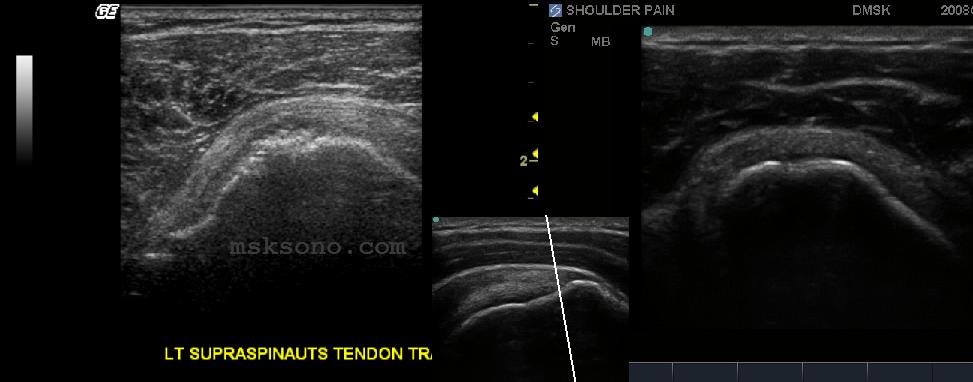

Right: Transverse Supraspinatus

at its distal insertion. Care must

be taken not to let anisotropic

artifact give false positive tears.

Image on left shows a distal tear

at the anterior insertion with

cortical irregularity.  The cortical

irregularity is the first indicator to

look for tears.  Take care not to

compress useful tissues with the

probe.